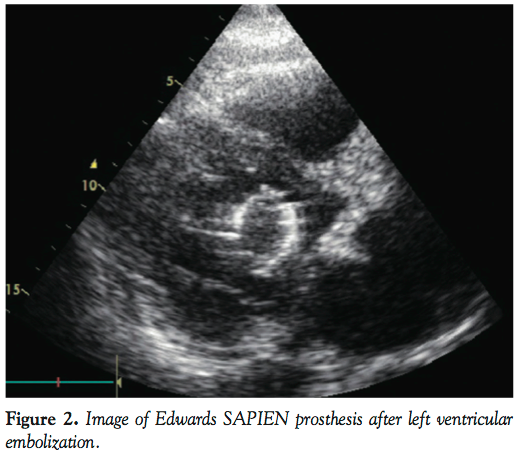

echocardiography demonstrated that the valve was dislocated with obstruction of the left ventricular outflow tract (LVOT). The device was holding on to the anterior leaflet of the mitral valve and there was severe mitral insufficiency. The patient did not respond to the inotropic treatment and required resuscitation, during which the valve embolized into the left ventricle (Figure 2). The patient improved following the embolization and he was urgently taken to the operating room. The valve was removed through the native aortic valve (Figure 3). The surgical repair was successful and the patient’s functional capacity improved to NYHA class 1 in 3 months.